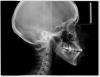

Skip Опубликовано 3 августа, 2012 Поделиться Опубликовано 3 августа, 2012 Здравствуйте, Юля. Вариант с удалением 4-ки мне не нравится. Не нравится по нескольким причинам, а в частности меня интересует механика, с помощью которой будет проводится последующая ретракция передних зубов. Там будет необходим абсолютный анкораж, а у меня есть большие сомнения в том, что для этого будут использоваться минивинты, учитывая что проходите лечение в муниципальной полуклинике. Я всегда оказываюсь в крайне для себя затруднительном положении, когда ко мне приходят пациенты на этапе уже проводимого лечения. Тем более такого лечения, когда даже не был поставлен диагноз (читайте между строк). Вы же сами теперь убедились, что необходимо было сделать прежде, чем инсталлировать брекет-систему, не говоря уже, о принятии решения удаления отдельных зубов. Но, 8-ки вверху удалять однозначно и делать это нужно не по окончании лечения, а уже сейчас.. Внизу тоже, но какую точно, нужно смотреть, возможно обе. Но опять же, речь сейчас не должна вестись вокруг отдельных зубов, это дело техники (тактика ортодонта). Речь о том, как Ваш лечащий врач видит стратегию (логика ортодонта) лечения:1) Патологии прикуса Класс II-I, высокий угол с тенденцией к открытому прикусу.2) Вправляемого вывиха диска. http://s015.radikal.ru/i333/1208/ae/7419e042feaf.jpg Интересно, почему Ваш доктор решил удалять 8-ки в конце лечения? Сейчас с увернностью могу сказать, что он понятия не имеет об окклюзионной плоскости и как работать с этой плоскостью при патологии Класса II/открытый прикус. Иначе, это удаление было бы перед началом лечения и ставило бы определённую задачу. Сейчас нужно заниматься положением языка и установлением правильного типа глотания, т.к. это предопределит положение шейного отдела позвоночника, головы, нижней челюсти, суставов, а также функции дыхания. Удаление 4-ки на верхней челюсти и последующая ретракция фронта окажет крайне негативное влияние на вышеперечисленное, так верхняя челюсть находится в ретропозиции. Положение языка, при данной патологии, является критическим. Это также будет оказывать влияние и на ретенции полученных результатов.Симметрии центра, после удаления верхней 4-ки, тоже врядли добьётесь. Кстати, сходите к ЛОРу, пусть дадут своё заключение. Что доктор собирается проводить на нижнем зубном ряду? Как будет проводиться апрайтинг и дистализация 7-ок без удаления 8-ых? Или также, как на верхней, прицепят дугу и будут ждать чуда от дядюшки Даймон? Ссылка на комментарий

Skip Опубликовано 3 августа, 2012 Поделиться Опубликовано 3 августа, 2012 простите, а что за методика анализа ТРГ? где про нее прочитать можно?)Прочитать негде, приезжайте в Волгоград и научитесь тому, как за 5 минут по ТРГ определить положение, размер, и соотношение челюстей, как и многое другое, что необходимо для диагноза и выработки стратегии лечения. В основе лежат анализы Сассуни и Риккетс. Ссылка на комментарий